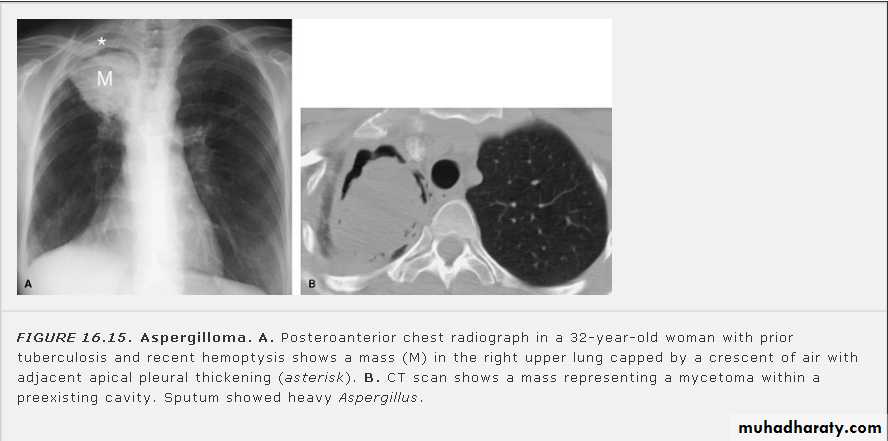

Fungus ball (air crescent sign)

Early rupture is sen as a cresnt air sign .ddx aspergillus ball